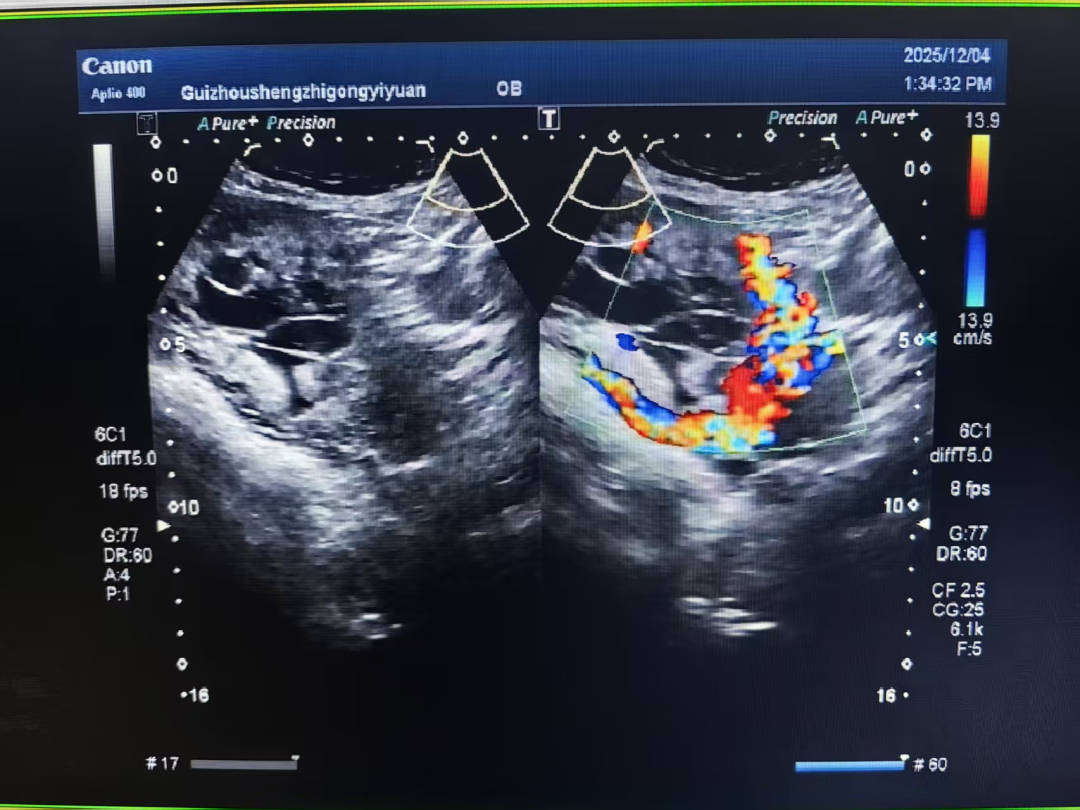

中央型胎盘前置状态合并胎盘植入是妇产科公认的凶险急症,犹如“定时炸弹”,易引发致命性大出血,严重威胁母婴生命安全。因该患者有多次剖宫产史,盆腔脏器存在严重粘连,增加了手术难度。患者入院后,我院第一时间启动多学科诊疗(MDT)模式,迅速召集医务部、妇科、介入室、麻醉科、泌尿外科、普外科、输血科、放射科等多学科专家联合会诊。

专家团队全面评估患者病情、结合患者需求,精准研判术中大出血、脏器损伤等高危风险,反复推演后制定“术前子宫动脉介入栓塞+双侧输尿管双J管置入术+子宫次全切除术”个体化救治方案。